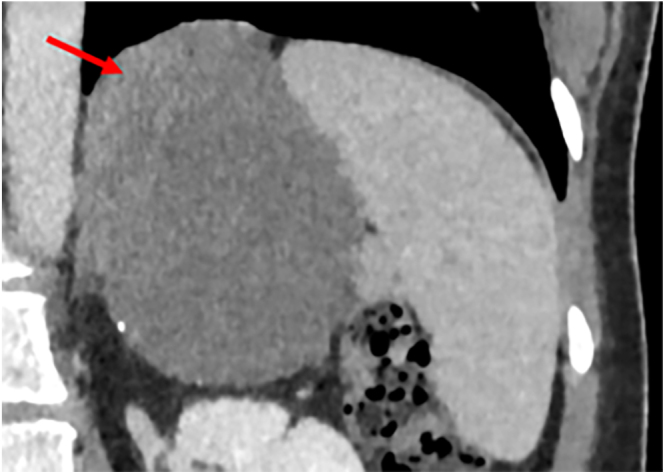

Summary: Bronchogenic cysts, developmental malformations of the primitive foregut, extremely rarely occur in the retroperitoneum. Here, we present a retroperitoneal bronchogenic cyst presenting as an adrenal incidentaloma and masquerading clinically as a phaeochromocytoma.

Learning points: Retroperitoneal bronchogenic cysts are exceptionally rare, particularly presenting as adrenal incidentalomas (AI), and can mimic other conditions such as non-functioning phaeochromocytomas. This case emphasises the need to consider rare conditions such as retroperitoneal bronchogenic cysts in the differential diagnosis of AI, especially when imaging findings are unusual despite normal hormonal studies. Atypical adrenal masses still warrant surgical evaluation and histopathological analysis to confirm the diagnosis and exclude rare entities. The occurrence of retroperitoneal bronchogenic cysts highlights the importance of understanding embryogenesis, particularly the migration pathways and foregut development. Histopathological examination remains crucial for diagnosing bronchogenic cysts, as they demonstrate the characteristic ciliated columnar epithelium with subepithelial smooth muscle, seromucinous glands, and cartilage.